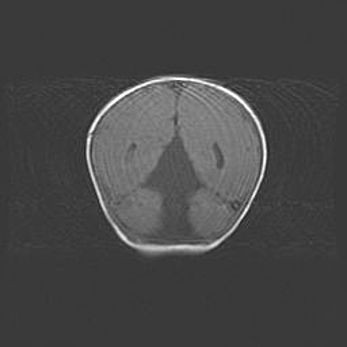

Подострая гематома правой гемисферы мозжечка.

Наружная гидроцефалия.

Возраст: 15 дней

Вес: 3100 г

Пол: женский

Окружность головы: 37 см

Срок гестации: 35-36 недель

При открытой наружной форме гидроцефалии у новорожденных расширяются и переполняются субарахноидные пространства.

Кровоизлияния в мозжечок имеют две клинико-анатомические формы: полушарные гематомы и кровоизлияния в червь.

К появлению этой патологии может привести: повреждения головного мозга, возникающие в результате асфиксии и гипоксии плода при беременности, или травмы во время родов. Редко гематома мозжечка может быть результатом первичной коагулопатии и сосудистой мальформации, диссеминированном внутрисосудистом свертывании, изоиммунной тромбоцитопении.